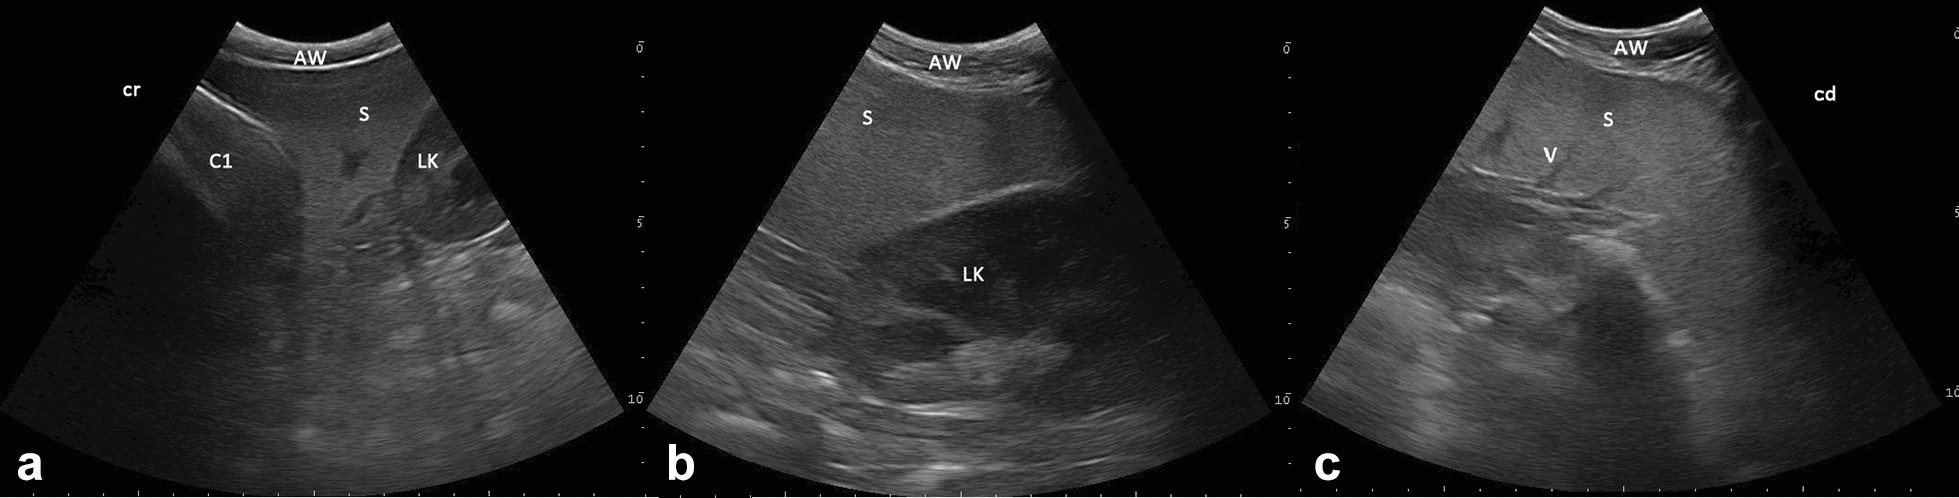

Sonographic appearance of the spleen in sagittal view in a 6 year-old alpaca. a The spleen (S), as viewed from the left paralumbar fossa, is caudal to the wall of compartment 1 (C1) and b craniolateral to the left kidney (LK). c The bend of the splenic tissue in the medial direction. AW abdominal wall, V vessel, cr cranial, cd caudal, 6.6 MHz